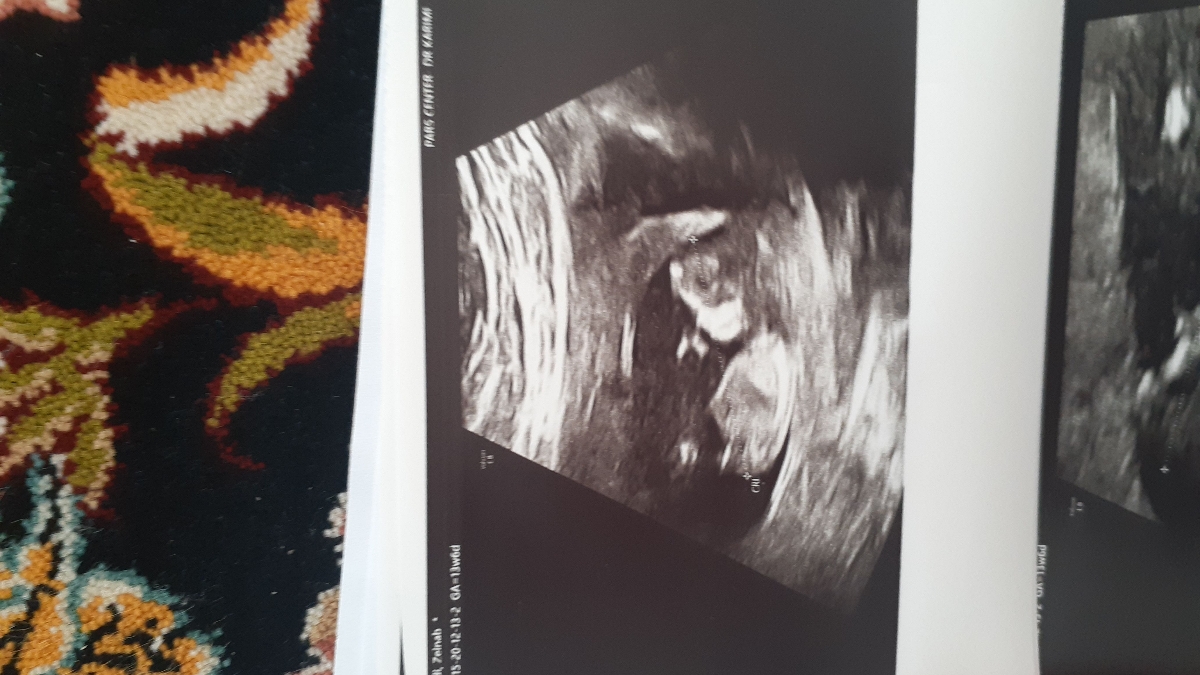

عکس سونوت بفرس

1

این دختره

این پسره